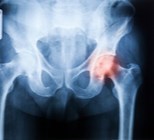

האם ניתן להבטיח שאורך הרגליים יהיה שווה לאחר ניתוח להחלפת מפרק הירך וכיצד הניתוח עשוי אף לטפל בבעיות הקשורות לפער באורך הרגליים?

שלום רב ממה שתיארת לא ניתן להגיע לאבחנה אבחנות באורטופדיה והמלצות לטיפול נעשות לאחר קבלת היסטוריה רפואית , בדיקה פיסיקאלית ועיון בהדמיה באם יש צורך יכול להיות ומדובר בתוגבה דלקתית (לא זיהום) בסטרוקטורות של בירך בורסיטיס כוונה לגירוי דלקתי במעטפת שנקראת בורסה, המעטפת מצויה במפרקים גדולים כל " בעיה בגוף" יוצרת תגובה דלקתית אשר מטרתה לנסות ולתקן את "הבעיה" בתגובה הדלקתית מפרשים חומרים אשר גורמים לכאבים NSAIDS או שמם האחר תרופות לא סטרואידליות נוגדות דלקת , גם מדכאות את הכאב בנוסף לדלקת, תרופות אלה ניתנות ללקיחה לפרק זמן קצוב סטרואידים-תרופות נוגדות דלקת. זריקות סטרואידים משמשות להקלה זמנית בלבד של כאבים.ודלקת (דיפורספן,דפומדרול, הידרוקורטיזון) יש צורך באבחון האם אין זה כאב מוקרן לדוגמא מהגב טיפולים דלקת/לבורסיטיס יכולים לנוע בין תרופות, זריקות, רפואה משילמה,, פיזיותרפיה, בברכה ד"ר בנימין בנדר www.drbender.co.il